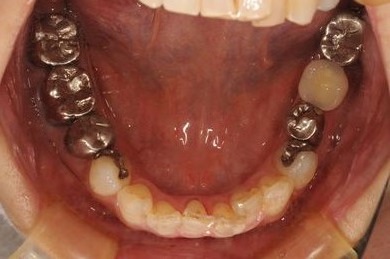

骨再生インプラント治療+セラミック治療

| 治療内容 | インプラント1本、メタルボンドセラミッククラウン2本、GBR | ||||||||||||||||||||||||||||||||